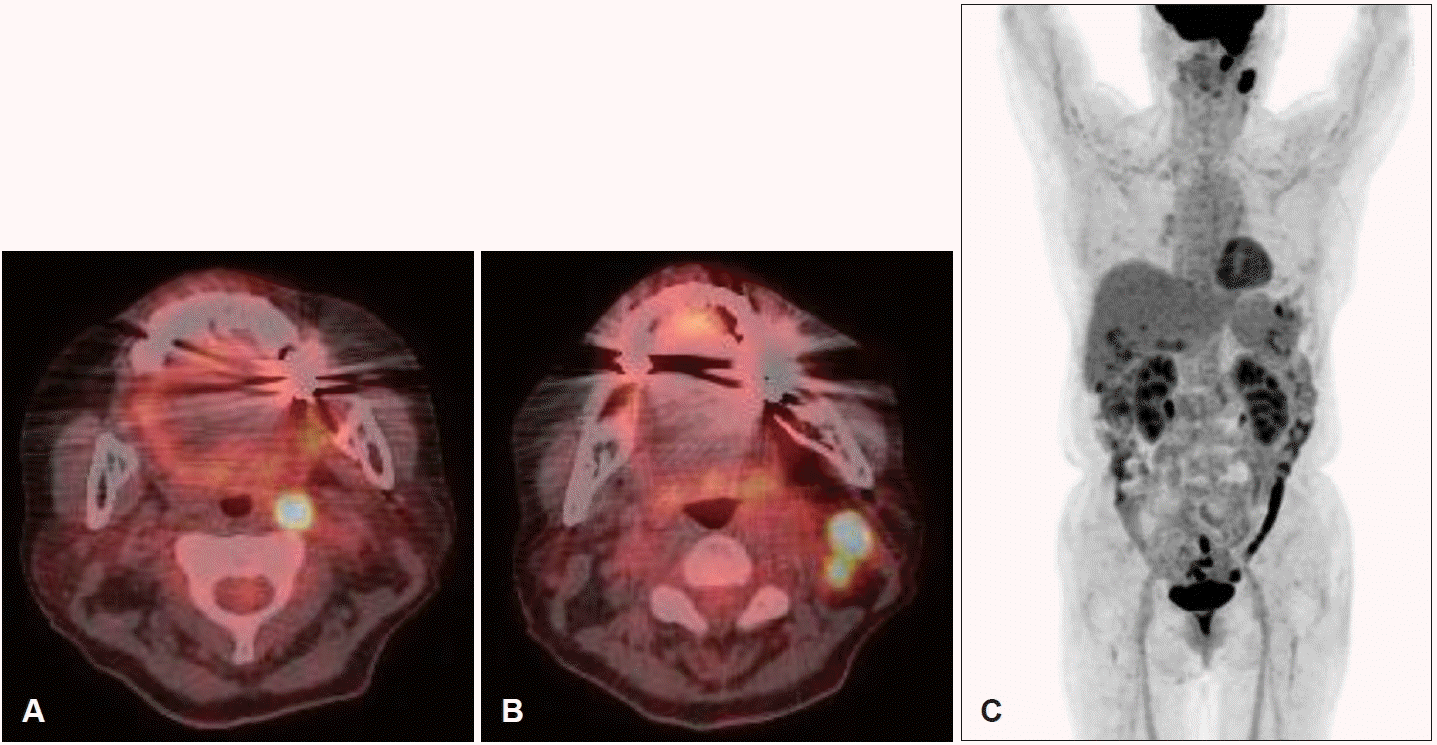

조직병리검사에서 두드러진 핵을 가진 다형성의 큰 종양성 세포가 관찰되었고, T세포 표지자인 CD3, CD45R0을 사용한 면역조직화학 염색에서 국소적 양성을 보였다. 추가적으로 시행한 면역조직화학 염색에서 CD30에 강한 양성을 보였으며 CD20, CD56, cytokeratin, ALK, smooth muscle actin, myoglobin, S100, HMB45에는 음성을 보여 결과를 종합하여 ALK 음성 역형성대세포림프종으로 최종 진단되었다(Fig. 3). 혈액학적 검사상 lactate dehydrogenase는 216 IU/L (106-211 IU/L)였으며 전신 전이 유무 평가 및 병기 결정을 위해 시행한 복부 및 흉부 전산화단층촬영에서 특이소견은 없었고, 양측 골반뼈에서 시행한 골수검사에서 림프종 침윤소견은 없었다. 염색체 검사에서도 특이소견은 없었으나 양전자단층촬영에서 좌측 경부 및 후인두림프절의 전이가 의심되는 소견이 있었다(Fig. 4).

Post-operative PET-CT of the patient. A and B: Post-operative PET-CT shows FDG uptake in the left retropharyngeal lymph node (A), and neck lymph node (B). C: Post-operative PET-CT suggests there is no distant metastasis with FDG uptake. FDG, fluorodeoxyglucose.

좌측 접형동에서 발생하여 경부 림프절을 침범한 Ann Arbor Stage IIE의 ALK 음성 역형성대세포림프종으로 최종 진단 후 6차례의 복합항암요법(cyclophosphamide, doxorubicin, vincristine, prednisone, CHOP)을 실시하였다. 치료 시작 후 3개월째 시행한 양전자단층촬영에서 접형동 및 경부 림프절의 종괴는 더 이상 관찰되지 않았으며, 최초 진단 후 13개월째 시행한 비내시경 소견상 수술부위의 재발 소견은 없었다(Fig. 5). 현재 최초 진단 후 16개월째 완전 관해 상태로 재발소견 없이 외래 추적 관찰 중이다.